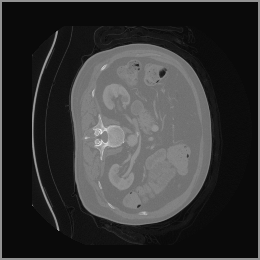

The motivation for this work arises from the need to address these limitations in the synthesis of 3D medical images. Current techniques do not produce high-resolution 3D images that preserve spatial coherence and capture the full complexity of medical data, as shown in Figure 2, 5. The development of advanced 3D generative models tailored specifically for medical imaging could not only improve the quality of synthetic medical images but also help alleviate data scarcity, enhance privacy protection, reduce computational requirement and ultimately advance the use of deep learning in healthcare applications.

To demonstrate the advantages of 3D semantic image synthesis over 2D semantic semantic image synthesis, we conducted a detailed comparison with the SegGuidedDiff [26] model. SegGuidedDiff generates medical images based on 2D semantic maps, producing individual 2D slices that are later stacked to form a 3D image. However, this approach has limitations in capturing spatial continuity and coherence across slices, which is critical for representing the spatial structure of 3D medical images. As a result, inconsistencies often arise between different slices, particularly in preserving anatomical structures across the coronal and sagittal planes. The generated images exhibit varying levels of denoising, resulting in differences in brightness and sharpness across the images. This inconsistency in denoising can lead to noticeable variations in visual quality, where some regions appear clearer and others less distinct.

As shown in Figure 5, the generated slices exhibit high consistency across adjacent slices. The anatomical structures and semantic patterns are smoothly and coherently preserved between slices, indicating that our model is capable of generating 3D-consistent synthetic images rather than isolated 2D slices.